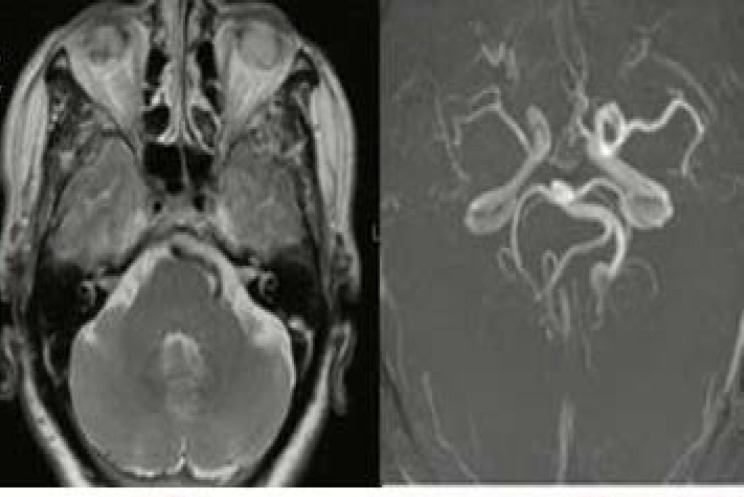

His brain magnetic resonance imaging (MRI) and MR angiography (MRA) in that hospital had shown dolichoectasia of distal segment of left cervical internal carotid artery and left vertebral and basilar arteries (Figure 2). The patient had been discharged with the diagnosis of "ptosis secondary to Dysport injection".

Figure 2.

Magnetic resonance imaging (MRI) and angiography revealed dolichoectasia of distal left internal carotid artery and left vertebral and basilar arteries, but no apparent aneurysm

In our patient, though ptosis developed one week after the injection, but was progressive and associated with severe aggravating pain. More importantly, detailed examination of ptotic eye revealed third cranial nerve palsy with irregular pupil. His brain MRI and MRA were unremarkable for a compressing lesion despite the presence of a PCOM aneurysm in the brain CTA. Therefore, MRA may not show small size aneurysms and a false negative result of 33% for PCOM aneurysm by MRA was reported previously.5 Therefore, in presence of high clinical suspicion to intracranial aneurysm as a cause of ptosis, brain CTA may be useful.